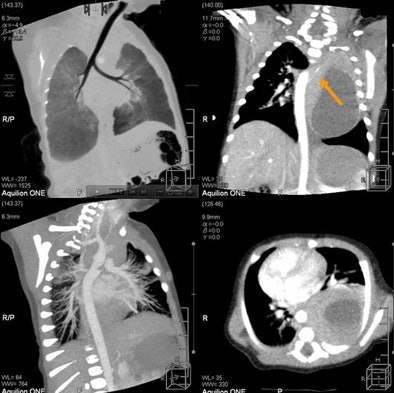

| Newborn with aortic hypoplasia and renal artery stenosis. Weight of 1.7 kg; single-rotation 320-detector-row scan at 0.5 sec, 80 kV, 40 mA, and dose of 0.3 mSv. All images courtesy of Dr. Patrik Rogalla. |